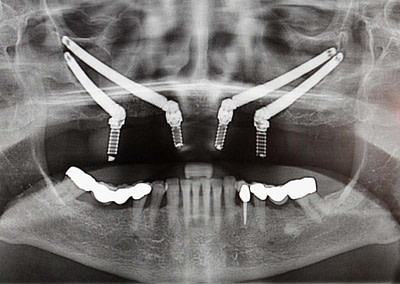

The Revolutionary Zygoma Implants at Rajan Dental

For patients who have experienced significant bone loss in the upper jaw, traditional dental implants may not be a viable option. Fortunately, Rajan Dental Clinic in Chennai offers an advanced solution known as zygoma implants, or zygomatic implants. These implants…

Navigating Your Options: Types of Zygoma Implants in Chennai

Are you considering zygoma implants in Chennai for a reliable dental solution? As you explore your options, it’s essential to understand the different types of zygoma implants available. Zygoma implants, also known as zygomatic implants, are a specialized type of…

The Science of Zygoma Implants: Restoring Your Natural Smile

A bright, confident smile is a true asset, and thanks to advancements in dental science, restoring it has become more achievable than ever. Zygoma implants are at the forefront of dental innovations, offering a remarkable solution to those seeking a natural and…

Zygoma Implants: A Game-Changer in Dental Restoration

The field of dental restoration has witnessed remarkable advancements over the years, improving the lives of countless individuals seeking solutions for missing or severely damaged teeth. Among the most significant breakthroughs is the development of zygoma implants —…

3D Technology & Zygoma Implants For Missing Teeth

For the first time in India a 3D printed surgical stent was used for a Quad Zygoma dental implant placement for a young female patient at Rajan Dental, Mylapore. This patient had lost almost all her upper jaw teeth by the age of 25. For this patient, quad Zygoma…